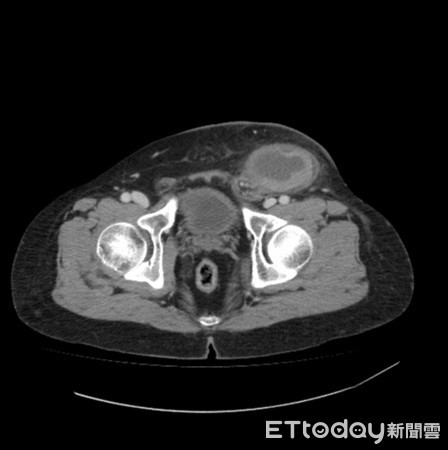

Theo trang Ettoday, một người đàn ông 46 tuổi ở thành phố Cao Hùng, Đài Loan đến bệnh viện trong tình trạng đau bụng dưới bên trái cấp tính. Sau khi khám, bác sĩ nghi ngờ bệnh nhân bị thoát vị bẹn trái và có thể bị hoại tử ruột. Tuy nhiên, sau khi tình cờ thấy bệnh nhân không có tinh hoàn, bác sĩ cho tiến hành chụp cắt lớp thì phát hiện ra phía bên trái tinh hoàn đang bị hoại tử. Do đó, bệnh nhân được chẩn đoán là bị tinh hoàn lạc chỗ, cần phải phẫu thuật khẩn cấp và may mắn là đã vượt qua cơn nguy hiểm.

Tố Kim Minh, trưởng khoa Tiết niệu, bệnh viện thành phố Cao Hùng cho biết: “Tinh hoàn lạc chỗ (Cryptorchidism) là do sự gián đoạn của tinh hoàn từ khoang bụng xuống bìu trong quá trình phát triển của nam giới. Điều này nghĩa là tinh hoàn không di chuyển vào đúng vị trí trong bao da treo phía sau dương vật trước khi bé trai ra đời".